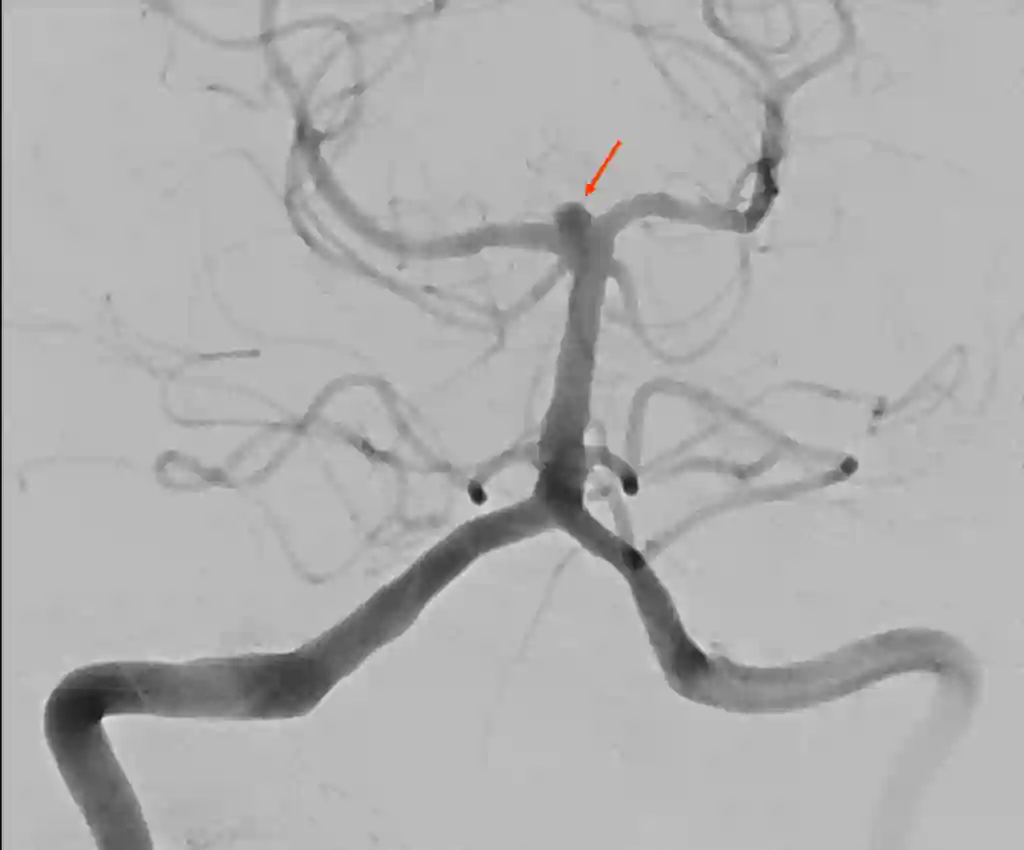

Angiographie der Arteria basilaris

Der rote Pfeil markiert die Arteria basilaris in einer Angiographie.